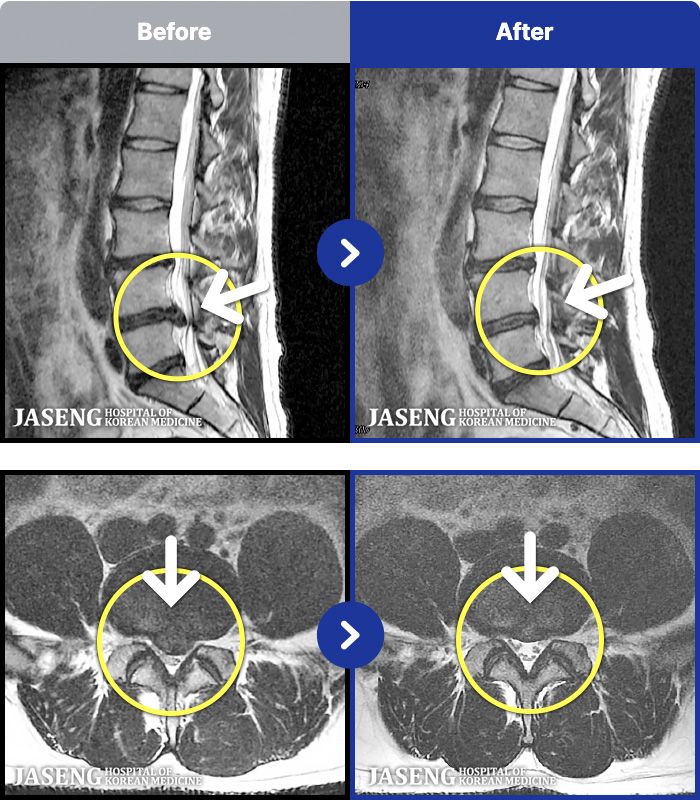

[뱸] 19.11.28~25.05.06

ȯںп Ǹ ǿ ԿǾ, ο ġ ۿ Ƿ ġḦ Ͻñ ٶϴ.